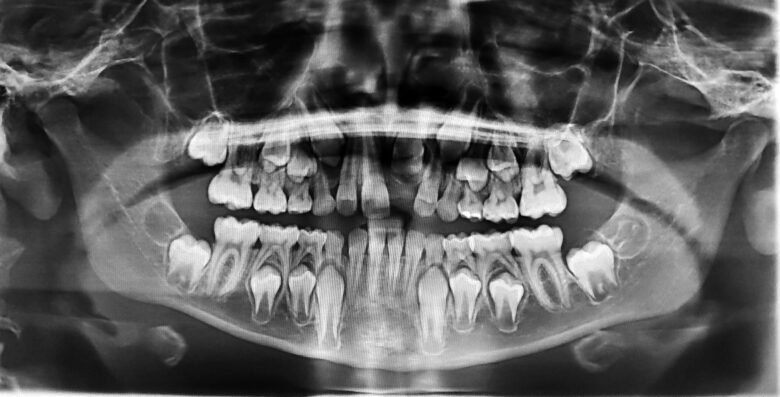

Antes da extração do siso, o dentista solicitará exames de imagem, como a radiografia panorâmica ou tomografia. Esses exames ajudam a visualizar a posição do dente, a proximidade com estruturas importantes (como nervos e seios da face) e possíveis complicações que podem surgir durante a cirurgia.